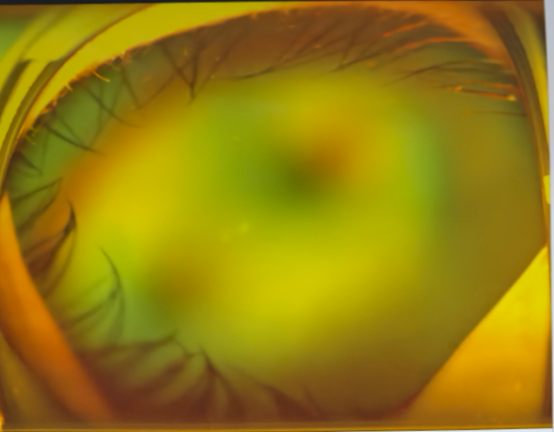

左眼術前△

左眼術后△